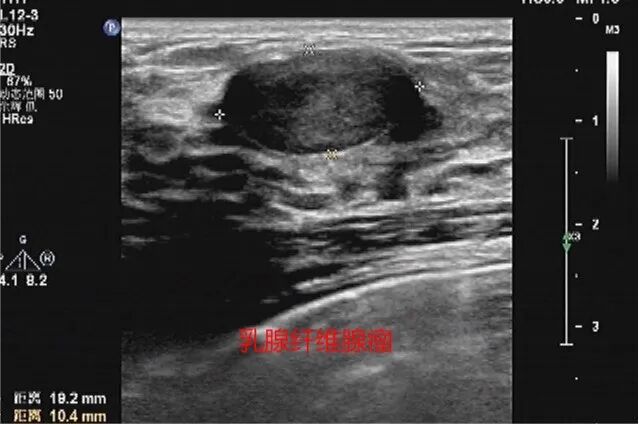

近日,年轻的王女士在体检中检查出左侧乳房上长了一个21*6mm的结节,超声提示结节为BI-RADS 3类。这个结果让王女士担忧万分,她没想到,二十出头的自己,乳房中竟然还隐匿着这样一个“小型炸弹”!联想到平日里从手机上看到那些“乳腺肿块未及时处理、最后演变成乳腺癌”的故事,她更加寝食难安。在朋友推荐下,王女士来到了泰州市第四人民医院就诊。

麦默通旋切术是在超声定位引导下,通过计算机控制的真空辅助高速旋切乳房治疗性诊断性微创手术,它可以准确的一次切除多个乳房肿块及对肿块进行病理活检,及时发现乳腺癌。